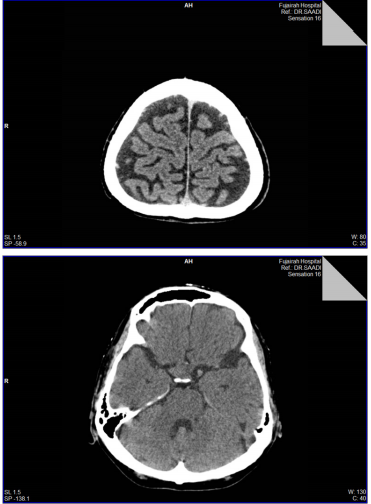

3. Urgent CT of head was performed and reported as: An ill-defined soft tissue density lesion in the supra-sellar region with possible sellar extension, No intracranial hemorrhage, or edema, no midline shift.., MRI is recommended with contrast for better delineation of this lesion... (MRI was not feasible because of Patient’ clinical status!)

2. CT Head & Sinuseswas taken and reported: there is no middle line shift, no edema or signs of inflammations, same previous findings...

CT- head nov. 20

1. The hyper density noted in the Pituitary Gland in the previous studies resolved completely, indicating that there is no fresh hemorrhage …

2. Normal brain parenchyma and ventricular system, normal cerebral sulci and basal cistern…